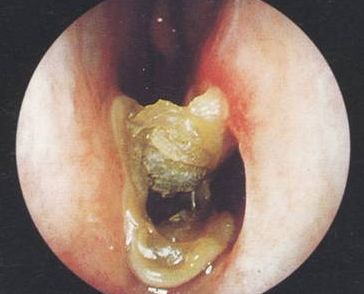

圖:萎縮性鼻炎的內(nèi)窺鏡圖